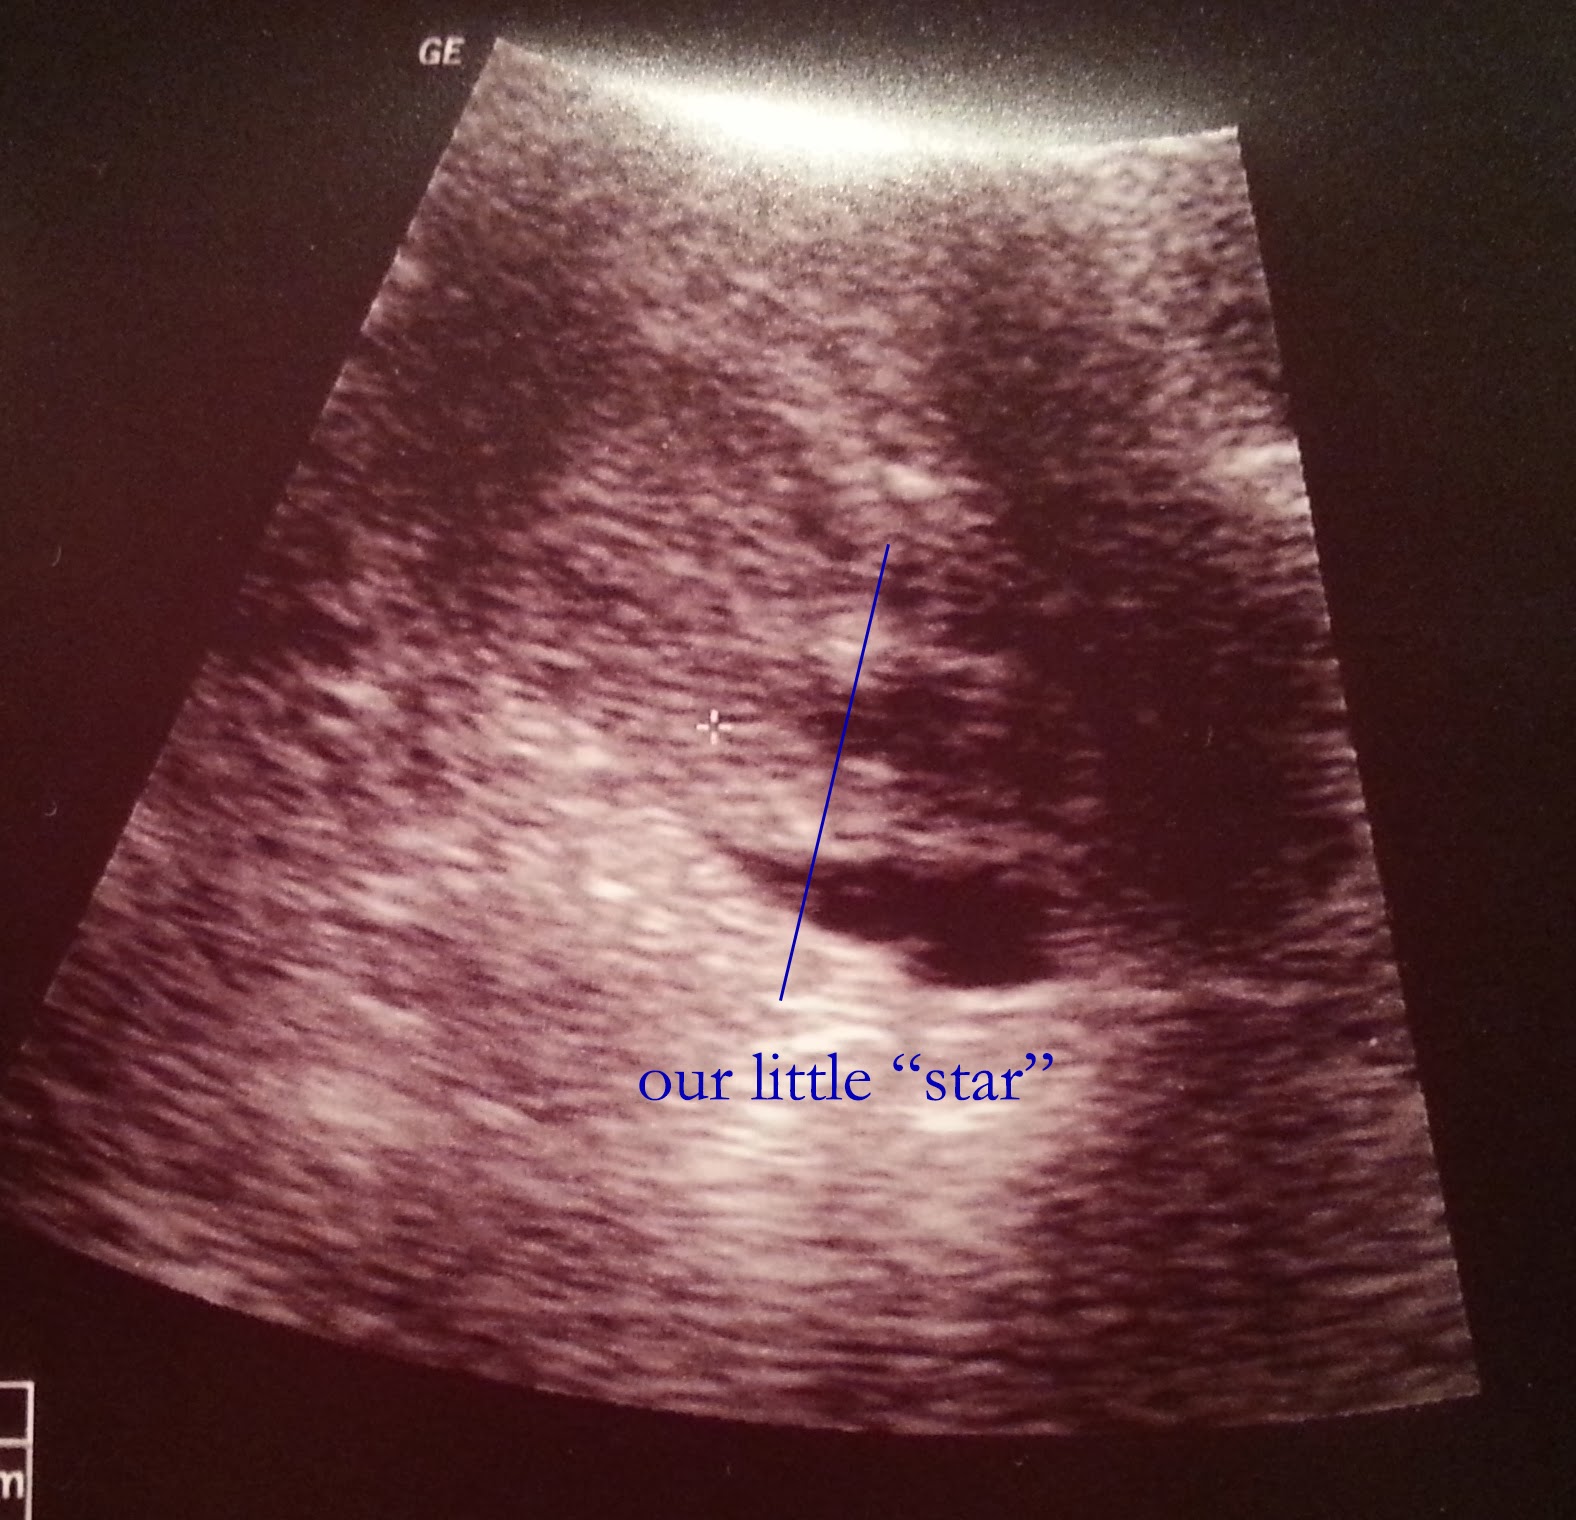

The embryologist confirmed my name and which embryo we were transferring (it happened to be #2 from our second retrieval). And we were ready to move forward again. The embryologist had our embryo in a pipette/thin straw which I *think* she then placed through the catheter while Dr. A positioned. To be honest, I wasn't watching what these women were doing because I was watching the screen. We could totally see when the little tiny ball of fluid (containing our embryo) was deposited in its spot. Amazing. Dr. A even got a picture of it for us:

And that was it!! The little bun was in the oven. It took maybe 15 minutes.